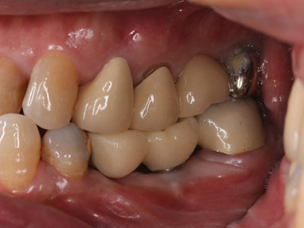

根管治療後は、クラウンと呼ばれる金属やセラミックの被せものを施し、歯冠修復を行います。

③ ジルコニアセラミクスクラウン(110,000円)

ジルコニアをフレーム(土台)とし、その上に審美性の高いセラミックを重ね盛った被せものになります。

ジルコニアをフレームとしているので強度が高く、表面はポーセレンという審美性の高いセラミックを重ねて作製するので、天然歯の色調を再現でき、自然な仕上がりとなります。